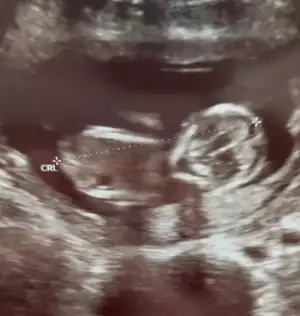

Erkek görünüyor

Yaaaa doktor kız demişti %85Erkek görünüyor![]()

Pardon cnm duzeltiyorum sanada erkek demis baska sayfada ❤Yaaaa doktor kız demişti %85bir oğlum var sağlıkla kız olsun çok isterim nub u kesin erkekmi

Kız görünüyorIkra meyra 12+4 canm

Tsk ederm canm önceki fotolarda erkek demistin ama sorun yok 1 ay sonra öğrenince oylayacagim anketiniKız görünüyor![]()

Önceki usg kaç haftalık bu kaç haftalik önceki daha net ise erkektir 11 12 13 haftalar olmalıTsk ederm canm önceki fotolarda erkek demistin ama sorun yok 1 ay sonra öğrenince oylayacagim anketini![]()

Ikra meyra gecen sene kizimi tahminde dogru bilmistin canim 13+3haftalik gebeyim tekrardan var mi bi tahminin